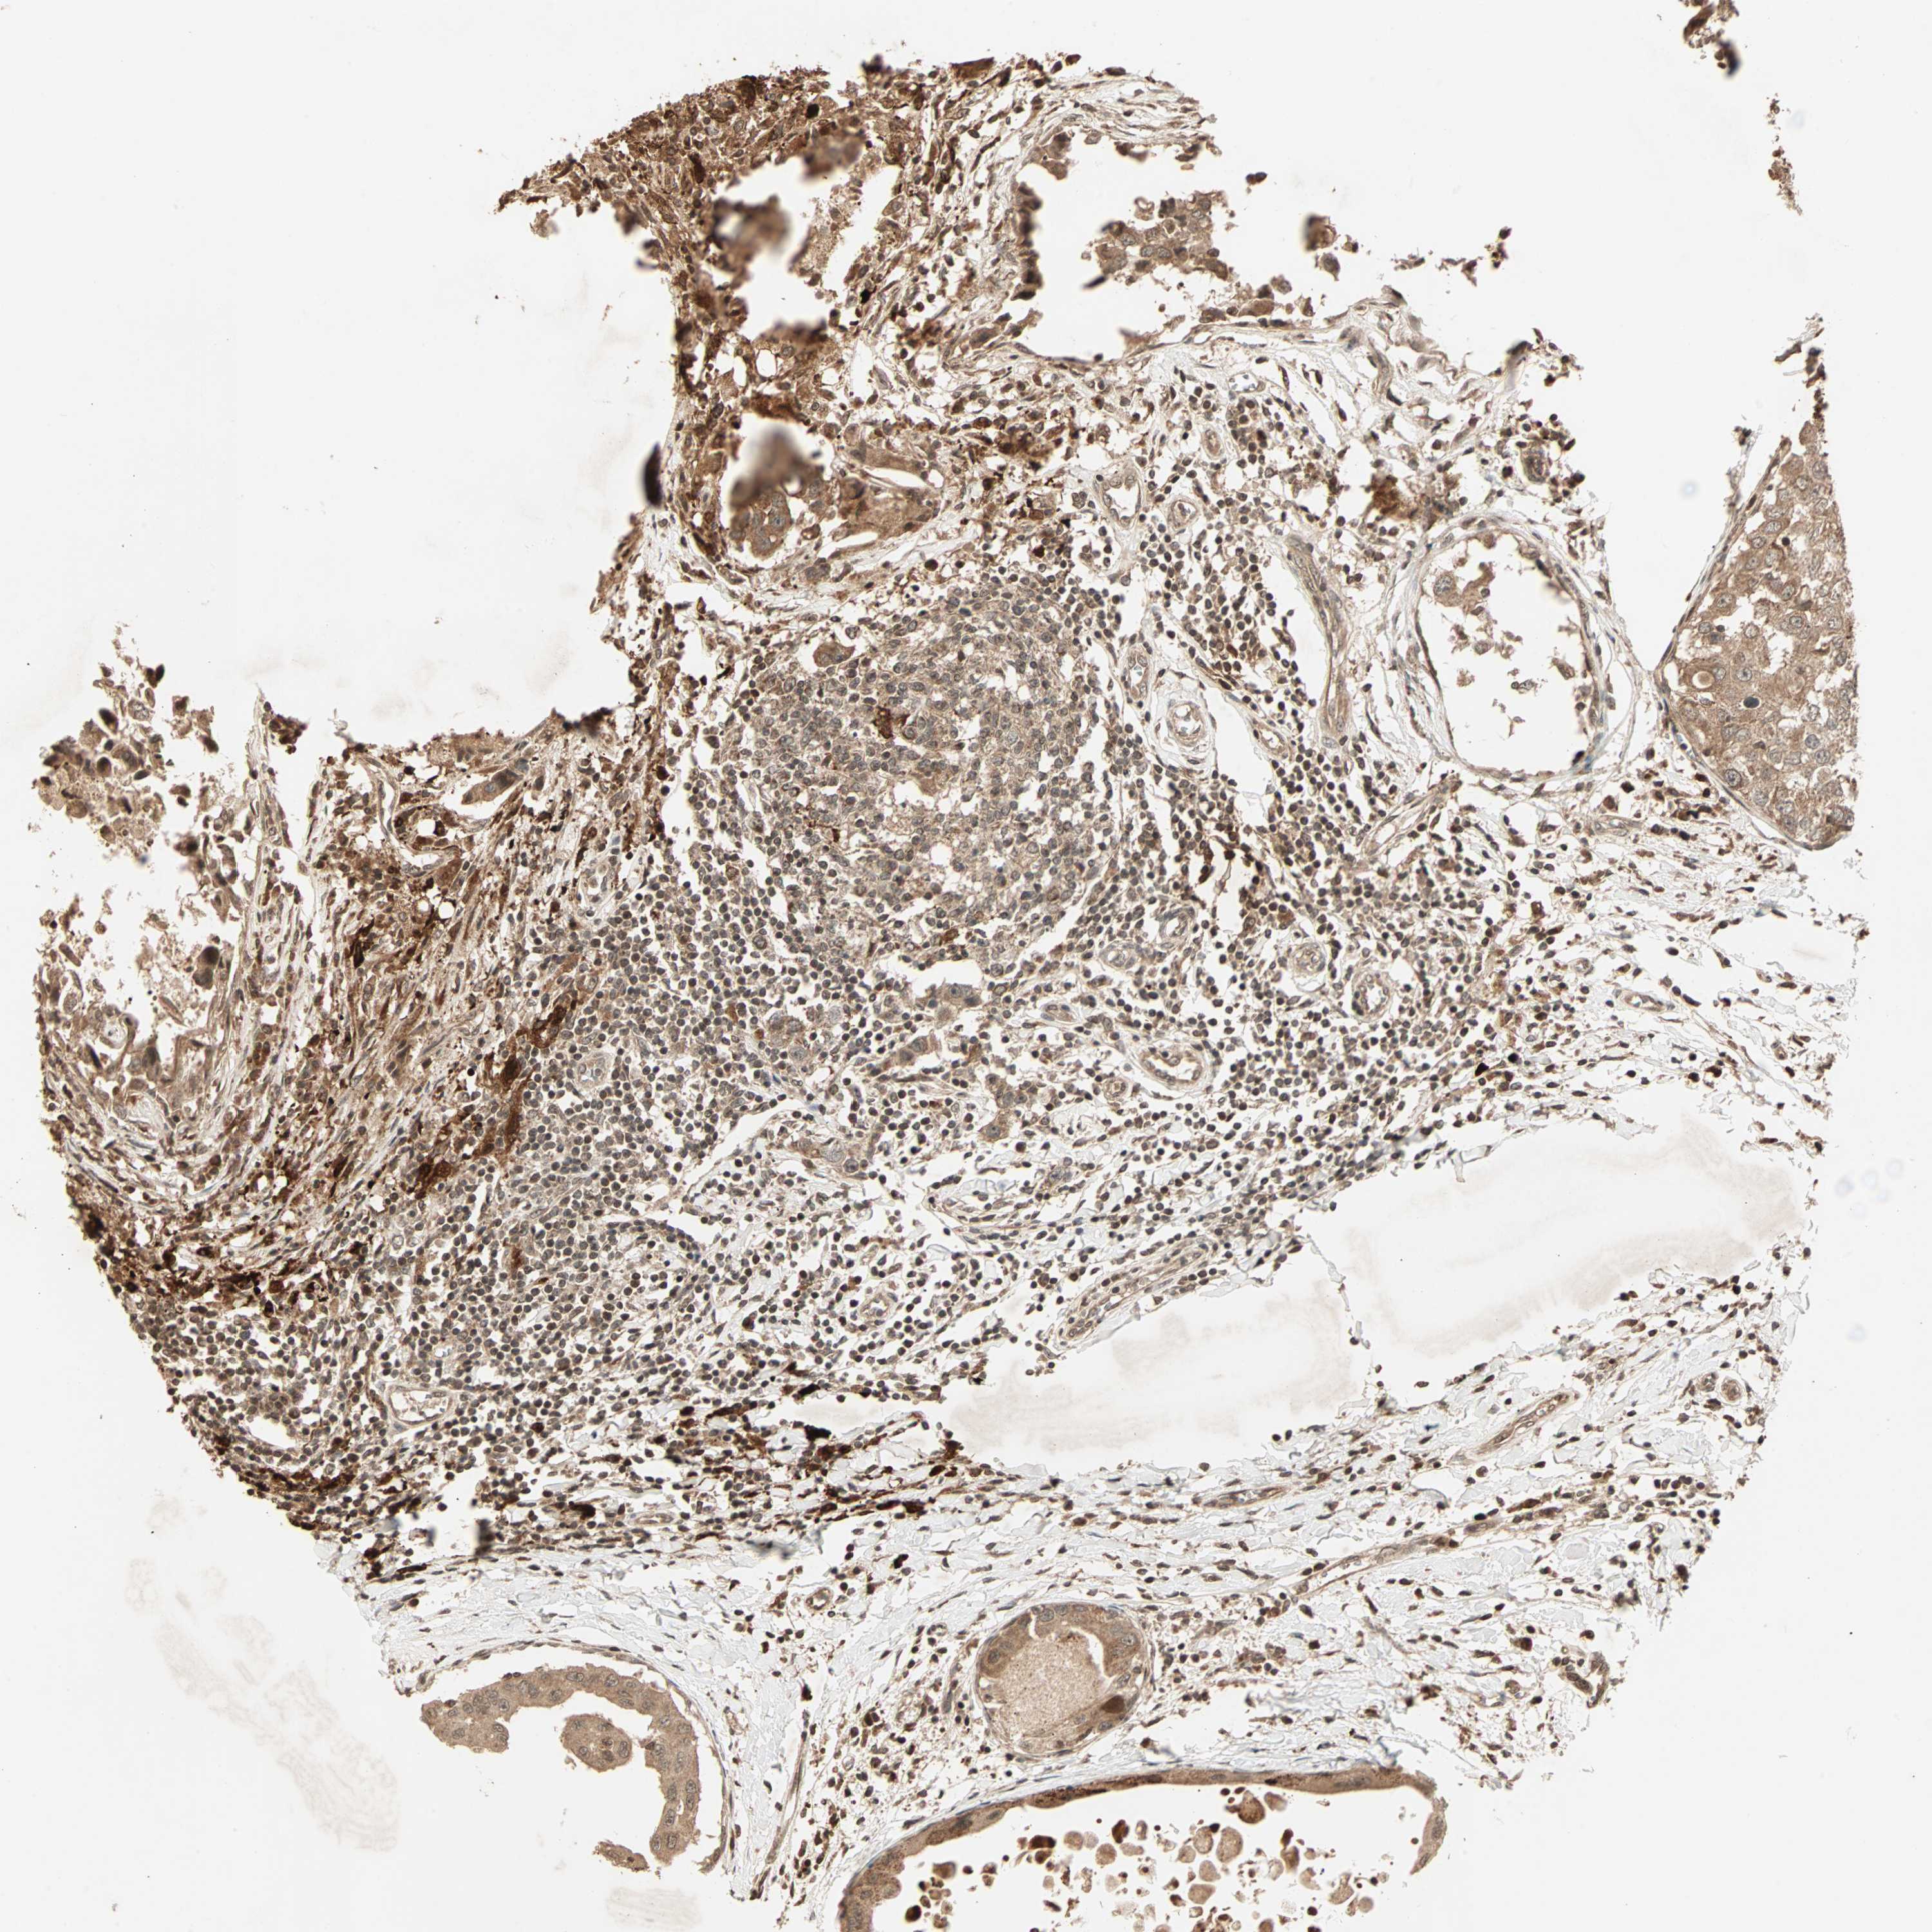

Breast cancer

Human cancer